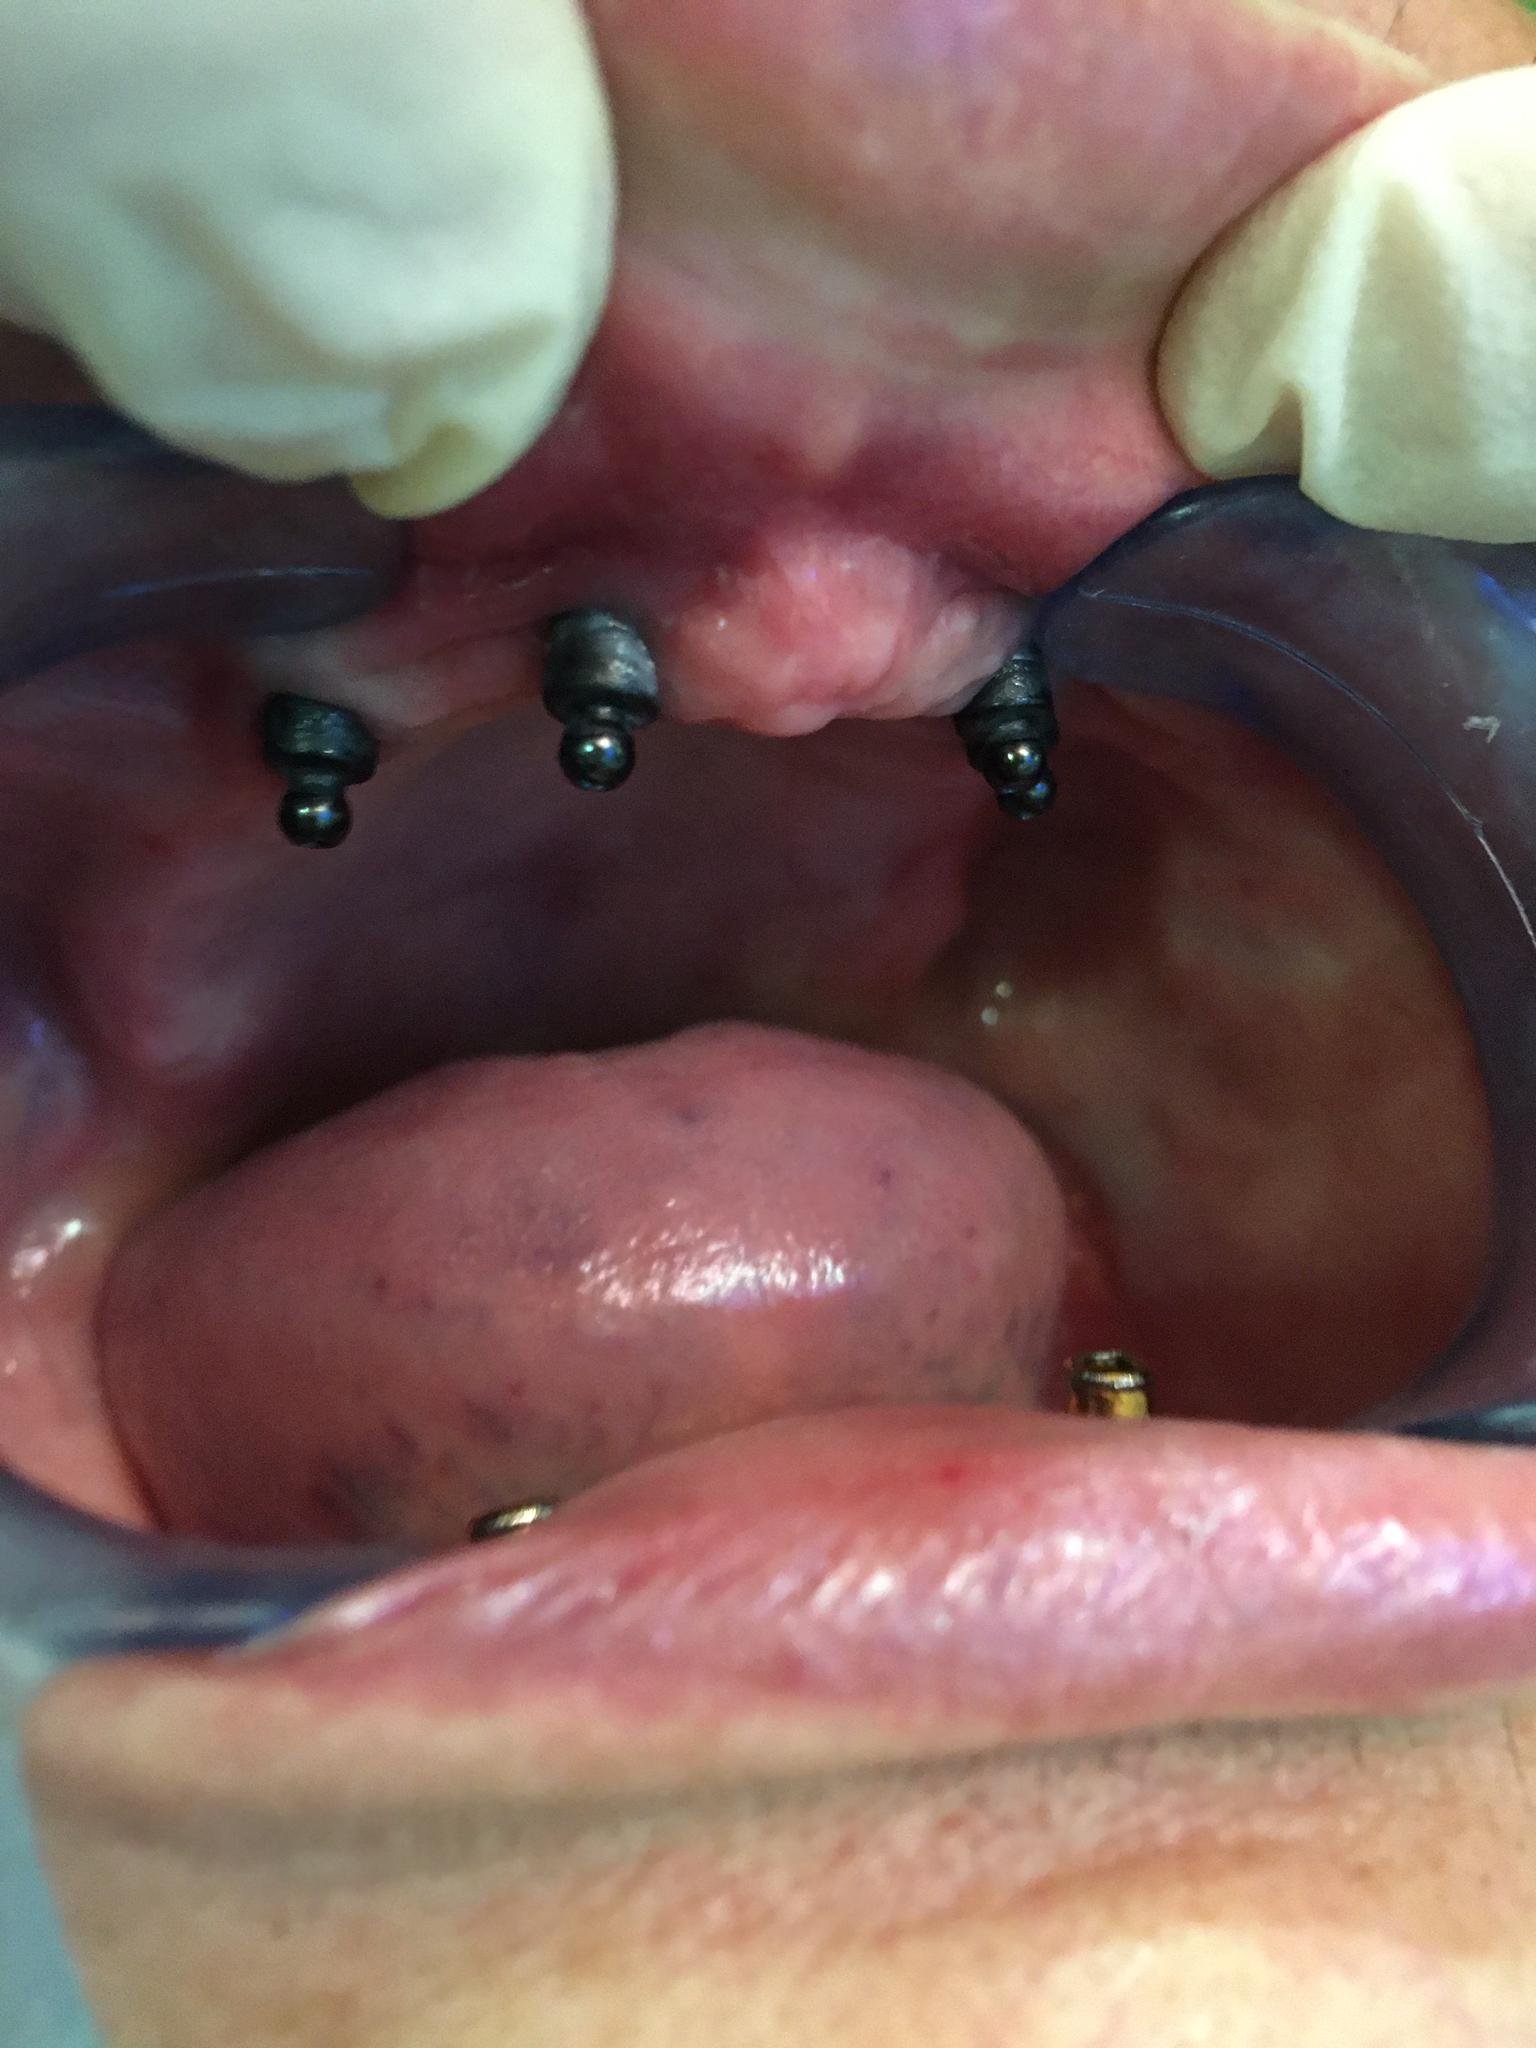

Una paciente de la clínica Odent , llevaba una híbrida que se rompió en boca y hay que hacer una nueva, no tengo ni idea de que implantes se trata, [...]